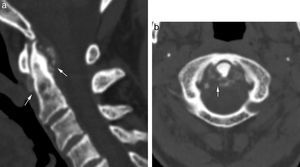

Tomografía computarizada multidetector con reconstrucción MPR en plano sagital de osteoartrosis multinivel que afecta tanto a la articulación atlo-odontoidea como a la columna cervical baja. Pérdida del espacio atlo-odontoidea, esclerosis subcondral y calcificación del ligamento apical (flecha negra larga). En el nivel C4-C5 presenta disminución del espacio intervertebral, osteofitos posteriores que improntan sobre el conducto espinal (flechas blancas).

Correlación en plano sagital de RM en secuencia FSE T2 (a) con tomografía computarizada en reconstrucción MPR (b) que demuestra osteoartrosis multinivel, discreta C1-C2 (*) y más grave en la columna cervical baja, especialmente en C4-C5 y C5-C6, osteofitos marginales (flechas), cambios en los platillos (cabezas de flechas negras) y deshidratación discal múltiple (cabezas de flecha blanca). Nótese la dificultad para diferenciar en la resonancia magnética el componente discal de los osteofitos comparando con la correspondiente imagen de TCMD.